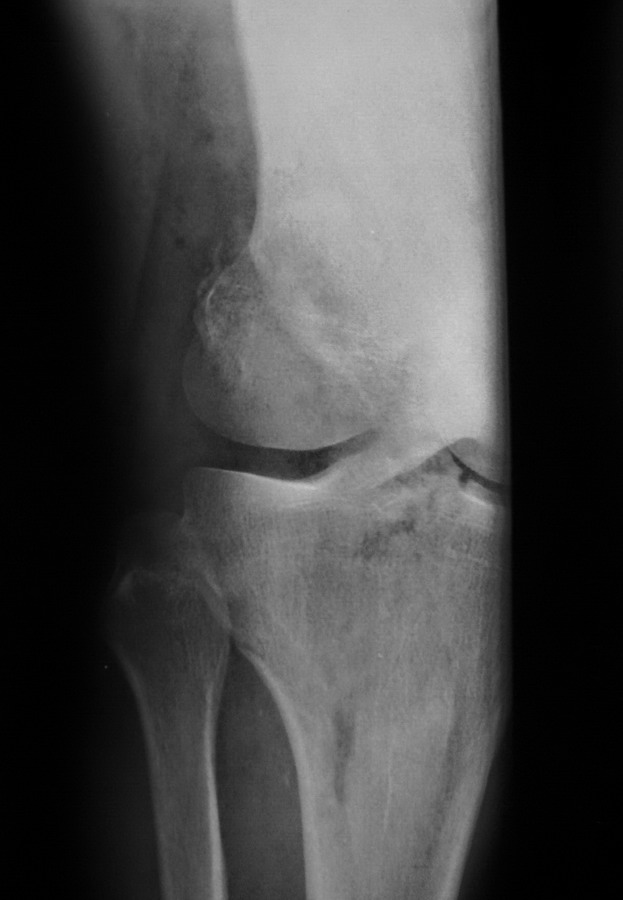

“Перелом наружного мыщелка правого бедра во фрональной плоскости был не замечен”

Диагностическая ошибка происходит, когда игнорируется правила обследования внутрисуставных переломов. Вместо полного обследования, включая КТ, ограничиваются рентгенограммой, и то в одной проекции!

Спасибо большое за советы! Добавляю некоторые КТ снимки. Перелом коллеги не диагностировали, видимо, расценив костную травму как повреждение задне-латерального комплекса коленного сустава. Отпишусь по результату выполненной операции.